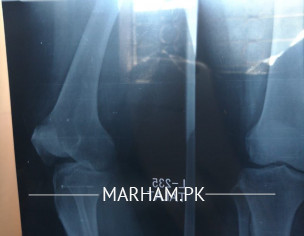

Asking For Someone else, Mother, Female, 50 Years old, karachi

she has severe pain in knee xray report are attached kindly tell me the problem and treatment my mother even cant walk i will b very grateful

It’s grade 2 osteoarthritis

AOA, in the X-ray shows patient suffering from osteoarthritis which cause the knee pain.

better get an appointment with an orthopedic surgeon for further examination, x-rays looks like grade 1-2 OA

X Ray images are improper. However, looks like she is suffering from knee osteoarthritis. She needs a thorough clinical evaluation.